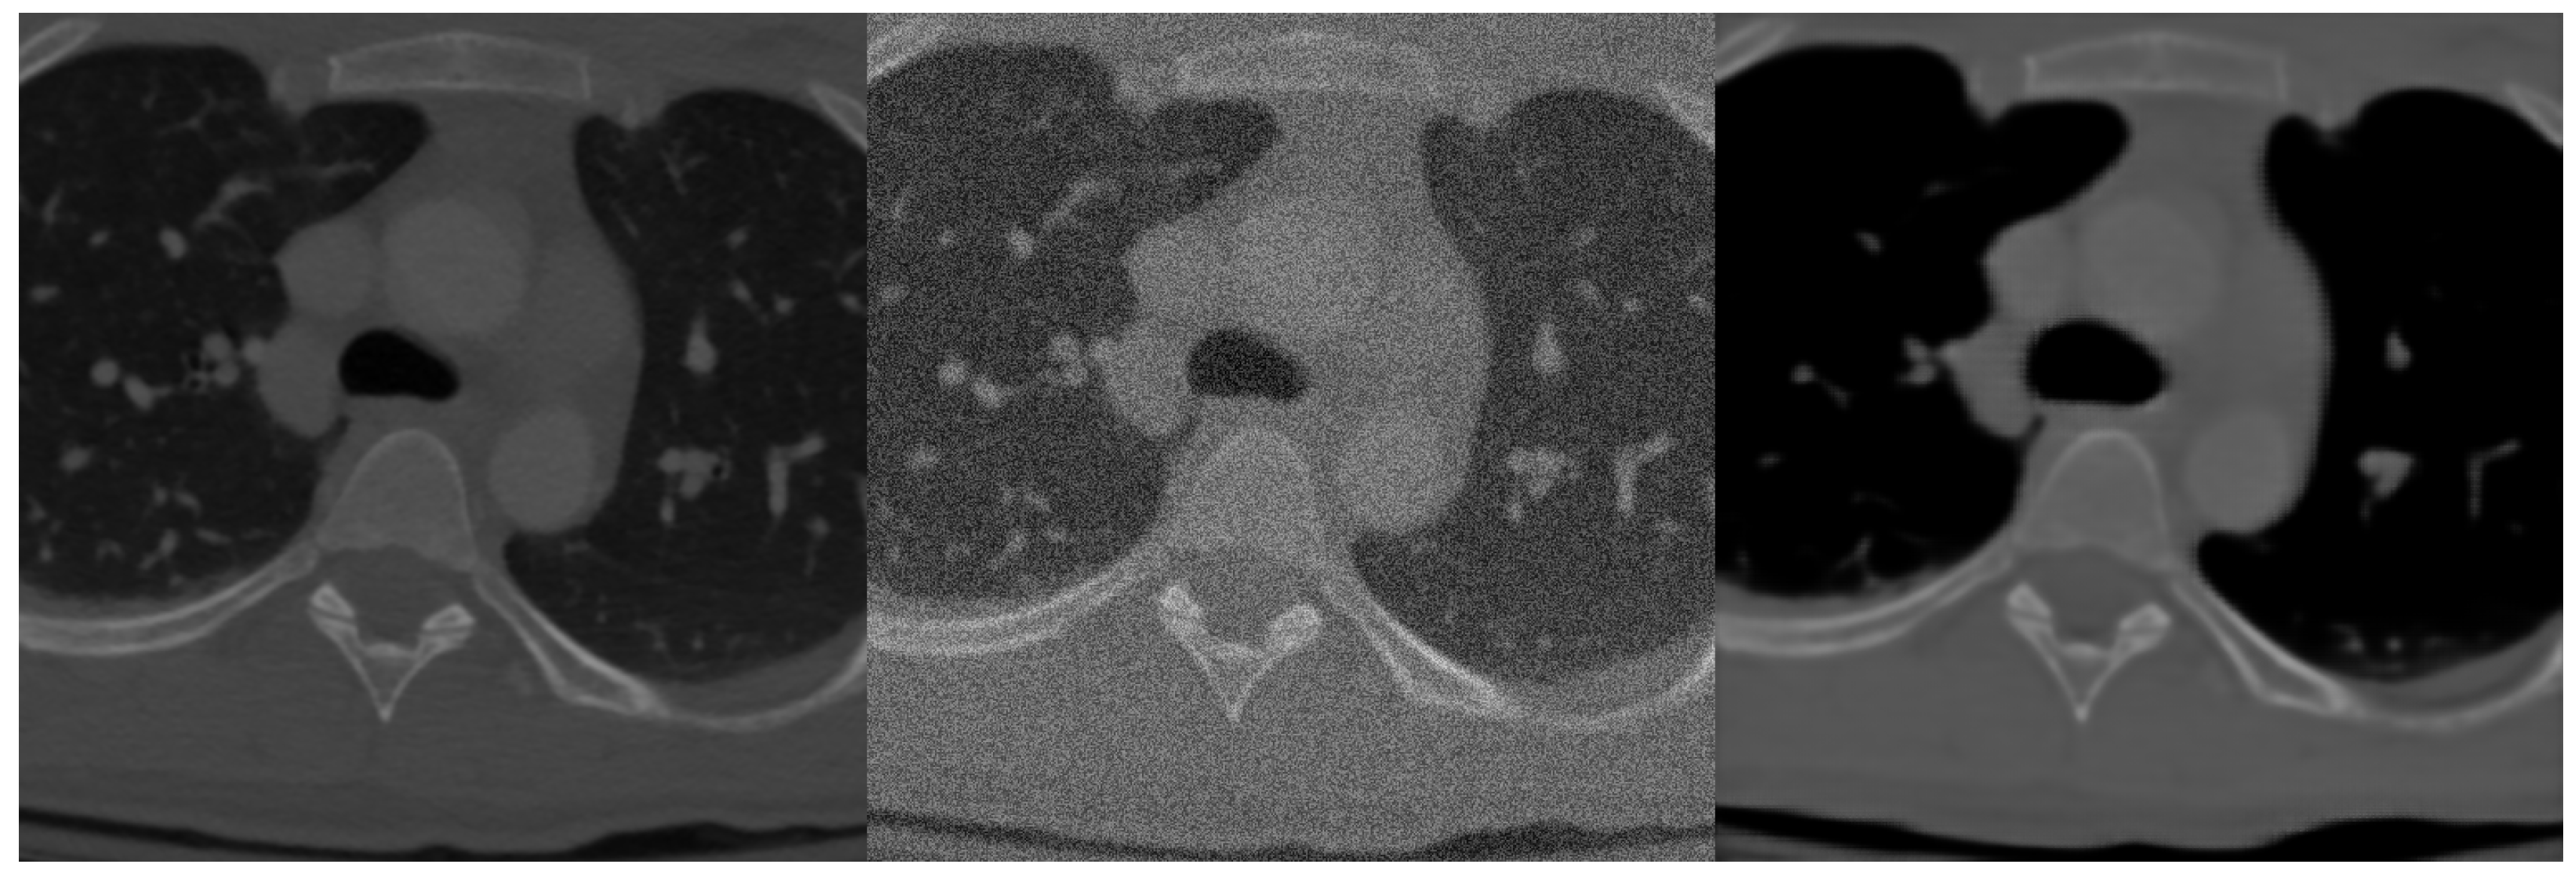

After initial segmentation experiments with the spine dataset we found it is a much more challenging task than the brain volumetric segmentation and training the network only on the dataset was not sufficient for highly precise segmentation. Instead of data augmentation, which for 3D algorithms greatly expands computation time, we used denoising autoencoder pre-training. Principle with this method lies in the fact that we add noise to the training data and let the neural network to learn the representation between noised and denoised data and therefore extracting features of the input image and proper learning of deep layers. An example of original training image, image with added noise and denoised image by our network can be seen in Figure 4.

Figure 4.

Example of data before adding linear noise (left), with added linear noise (middle) and after denoising by neural network (right).

Training dataset consisted of normal training data with added linear 30 percent noise with normal distribution. The network was trained to denoise data into its original form. As seen in Figure 4 the network learned the representation properly, denoised image only lacks higher level of details [20].